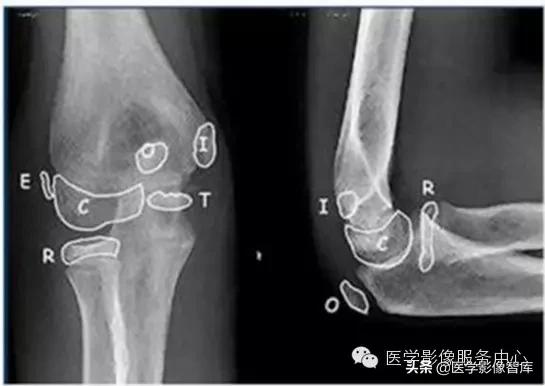

现在简单了,只要记住CRI TOE1-3-5-7-9-11就行了:

- Capitellum (appears age 1-2)肱骨小头1 year - Radial Head (appears age 2-4)桡骨小头 3years- Interanal epicondyle (appears age 4-6)内上髁 5years- Trochlea (appears age 8-11)滑车 7years- Olecranon (9-11 years)鹰嘴 9years- External epicondyle (appears age 10-11)外上髁 11years